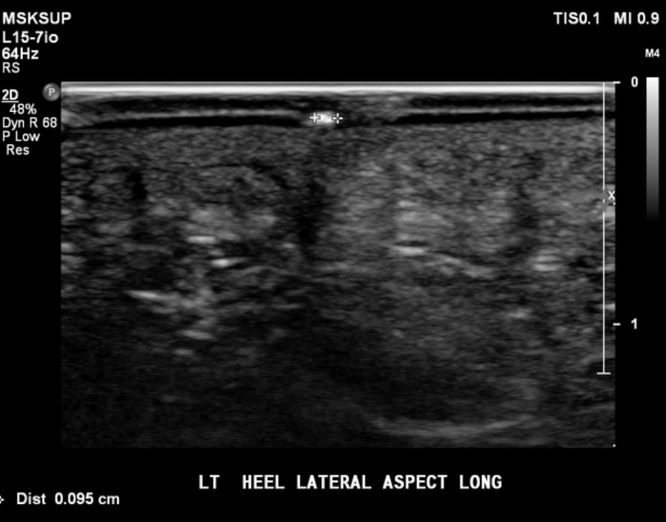

Figure 4: wooden splinter (between pointers) in a heel (from: https://radiopaedia.org/cases/foreign-body-in-heel-1?lang=us)

If the foreign body is wood or other organic material, it will appear echogenic and may cause posterior acoustic shadowing [3]

In this case, a hyperechoic foreign body with posterior shadowing was identified on ultrasound. After anesthetic was applied, a small incision was made in the skin that allowed for easy removal. The object was a small wooden splinter. Ultrasound was then used to assess and there was no remaining material so the patient was discharged.